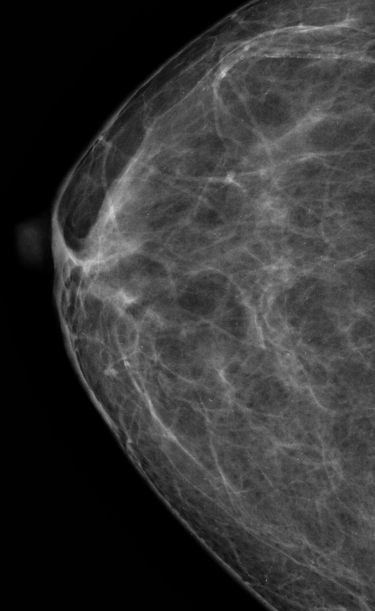

Mastografia o mamografia para un diagnostico temprano

MASTOGRAFIA DIGITAL

Radiología Digital y Mamografia

Contamos con tecnología avanzada para diagnósticos precisos y confiables en radiología digital.

Galería Médica

Explora nuestros servicios de radiología y medicina regenerativa.